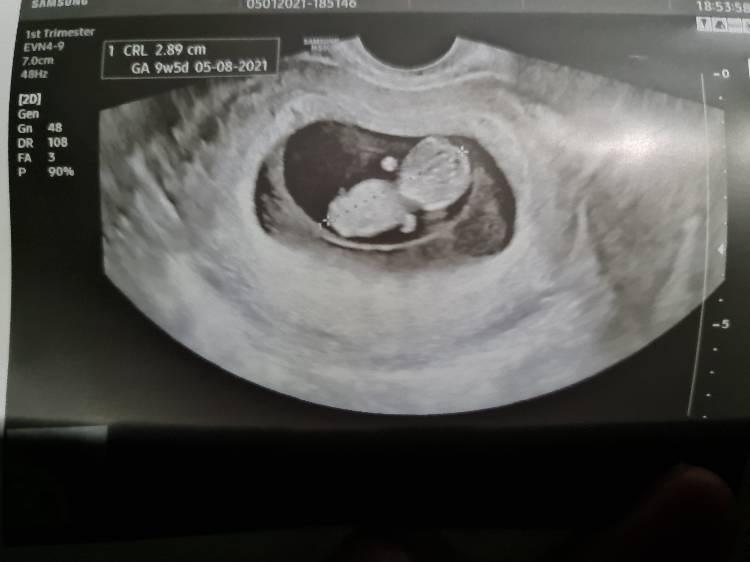

Ja juz tez po wizycie:) jak widać z usg 9+5 z om 10tc, serduszko 168/min, doktor powiedziała że wszystko wygląda bardzo ładnie.